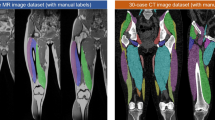

Recent developments in deep learning (DL) techniques have led to great performance improvement in medical image segmentation tasks, especially with the latest Transformer model and its variants. While labels from fusing multi-rater manual segmentations are often employed as ideal ground truths in DL model training, inter-rater variability due to factors such as training bias, image noise, and extreme anatomical variability can still affect the performance and uncertainty of the resulting algorithms. Knowledge regarding how inter-rater variability affects the reliability of the resulting DL algorithms, a key element in clinical deployment, can help inform better training data construction and DL models, but has not been explored extensively. In this paper, we measure aleatoric and epistemic uncertainties using test-time augmentation (TTA), test-time dropout (TTD), and deep ensemble to explore their relationship with inter-rater variability. Furthermore, we compare UNet and TransUNet to study the impacts of Transformers on model uncertainty with two label fusion strategies. We conduct a case study using multi-class paraspinal muscle segmentation from T2w MRIs. Our study reveals the interplay between inter-rater variability and uncertainties, affected by choices of label fusion strategies and DL models.

Roshanzamir, P., et al.: Joint paraspinal muscle segmentation and inter-rater labeling variability prediction with multi-task TransUNet. In: International Workshop on Uncertainty for Safe Utilization of Machine Learning in Medical Imaging, 14 September 2022, pp. 125–134. Springer, Cham (2022). https://doi.org/10.1007/978-3-031-16749-2_12